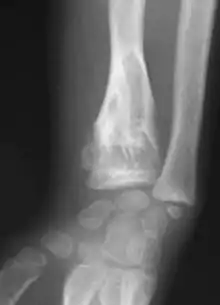

| X-ray image showing enchondromas localized in the lower part of the radius of a 7-year-old girl with Ollier disease. | |

Abnormal bone growth such as shortening or thickening and deformity may be observed in patients of Ollier disease. These bone lesions are visible at birth using radiography but are usually not screened or examined for until clinical manifestations present during early childhood. However, some patients may exhibit no signs of any symptoms.[1] One study found thirteen to be the mean age of diagnosis in patients with Ollier disease. In an X-ray, there would normally be the presence of several homogeneous lesions of an oval or elongated shape with bone edges that are slightly thickened.[3] With age, these lesions may calcify and appear as diffusely minute spots or stippled. Fan-like septations or streaks would be indicative of the presence of several enchondromas. Early detection and consistent and repeated monitoring is important in order to prevent and treat any potential bone neoplasms.